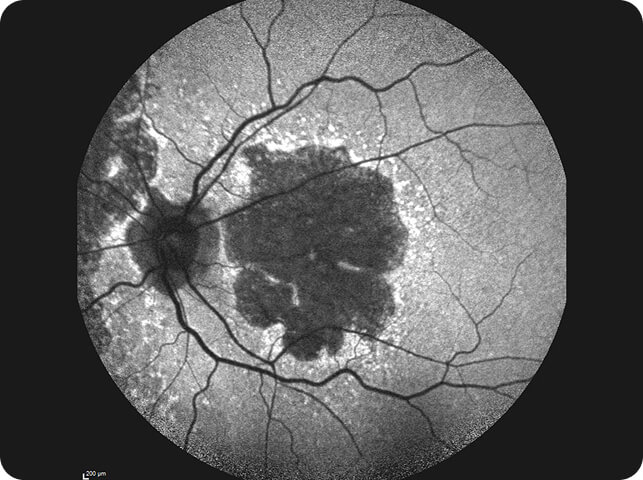

Fundus AutoFluorescence (FAF)

Many structures in the posterior segment possess innate fluorescent properties or “fundus autofluorescence” (FAF), that is, they fluoresce even in the absence of any exogenous contrast agent.

FAF imaging is an essential requirement for highly specialised retinal clinics. It plays a crucial role in the diagnosis and monitoring of patients with inherited retinal disease and in the assessment of patients with toxic retinopathies (e.g., hydroxychloroquine retinopathy).

It also has an emerging role in the diagnosis and monitoring of geographic atrophy in patients with “dry” AMD.